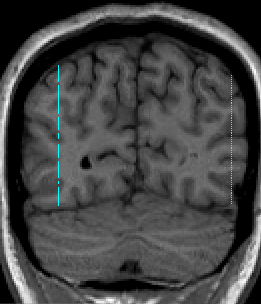

Combine the two coronal slice numbers and divide the result by two (if the result is not a whole number, then round up). Go to this slice number in the coronal view and note where the vertical crosshairs appear in the sagittal view. On the same sagittal slice that previous sulci lines had been drawn on Part 2 (here see Fig 9) draw a vertical line along this vertical crosshair (Fig 24). Do this for both hemispheres.

Figure 24